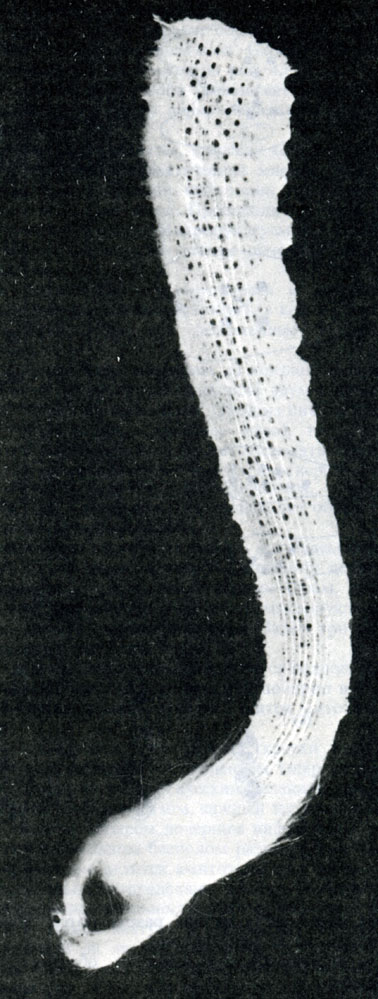

Визуальные материалы, связанные с болезнью Горхема-Стаута

Раздел: Альбом открытий